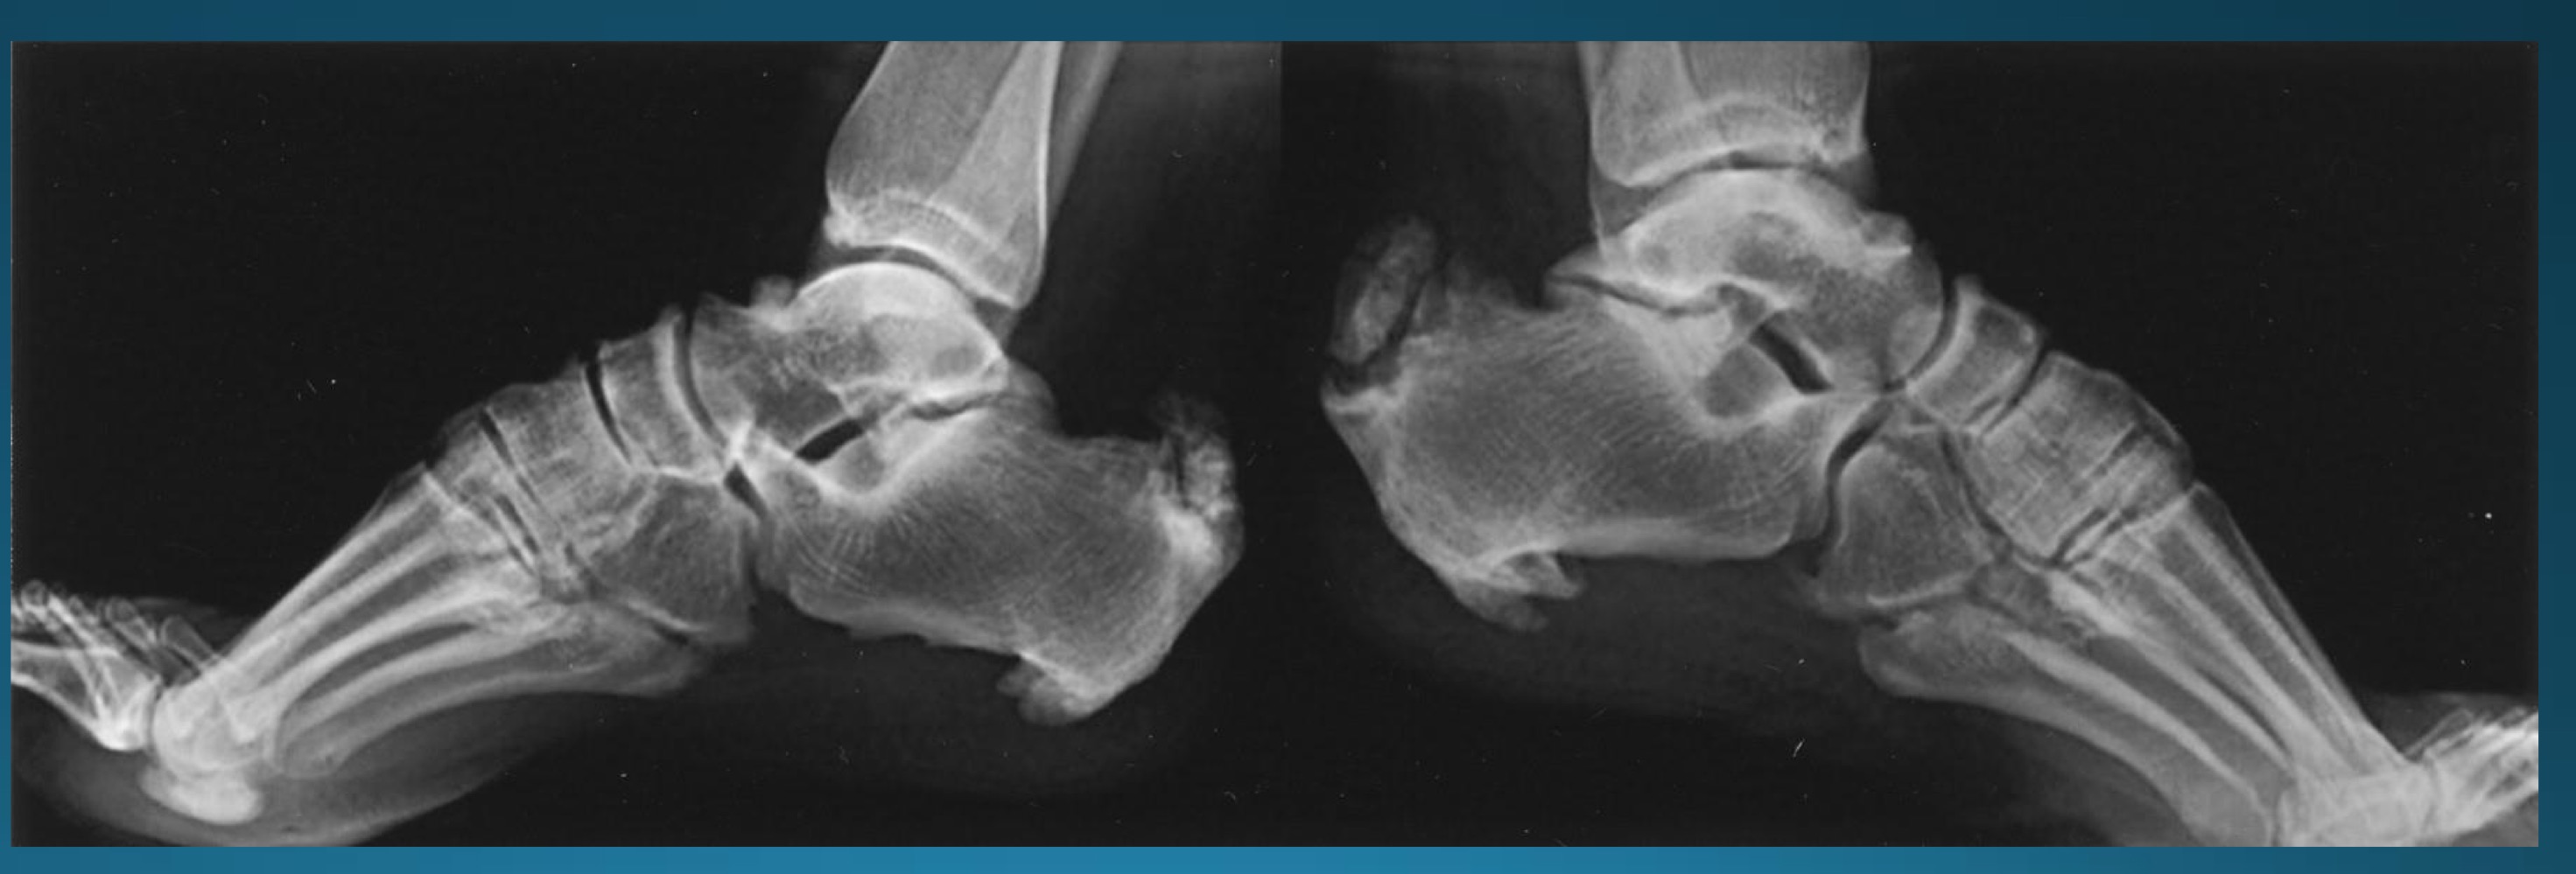

what is the finding in this radiograph? AKA?

OPLL/japanese disease

OPLL might present with what kind of issues? what symptoms would this cause?

neurological disturbance causing

heavy feeling legs

inability to walk and brisk pace

deterioration of fine motor skills

intermittent shooting pains into arms and legs

most common site of OPLL

cervical spine

is this a contraindication to adjusting? if so, what kind?

yes, absolute contraindication